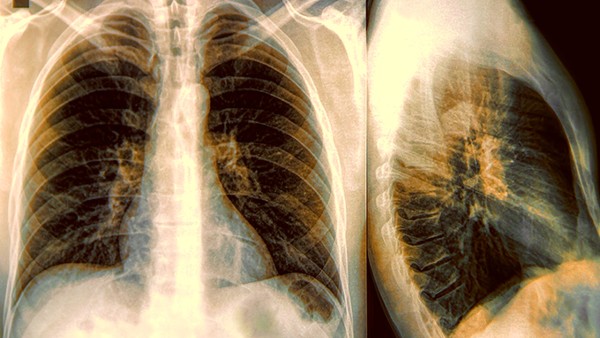

4.肺炎:主要是由细菌或者是病毒通过飞沫传播等方式进入体内所引起的肺部炎症病变,当身体抵抗力下降时,致病菌会大量繁殖,从而引发咳嗽、胸闷、呼吸困难等不适症状。可以遵医嘱服用利巴韦林片、磷酸奥司他韦胶囊等抗病毒药物来抑制病毒的复制,还可配合布洛芬缓释胶囊、对乙酰氨基酚片等解热镇痛药来帮助降温。